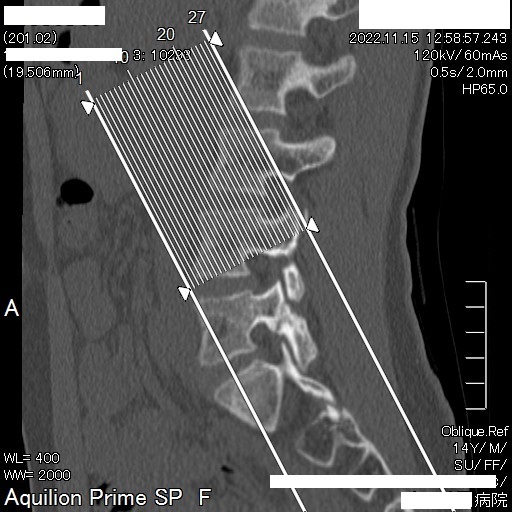

11月15日 再検査にて更に分離部位の癒合が認められるとの所見。現時点で腰痛や下肢疼痛など症状の再発は無し。

今回ご紹介する症例は、半年もの間一向に改善しなかった腰椎分離症がわずか1ケ月半の間に、しかも4回の施術で劇的な改善が見受けられたことについて、病院での一連の検査が終了した後に受療者の保護者より病院での検査記録の提供を受け、発症から治癒に至るまでの詳細について時系列でお伝えするものす。また、この症例はこれらの画像提供を受ける2ヶ月前の段階で既に筋肉反射テストにより損傷部位を正確に特定し、骨の癒合を促す施術を行った結果です。この目まぐるしい回復に専門医も只々驚愕しきりだったとか。本人は手術を受けるつもりでいたようですが、我が子の体にメスを入れることを良しとしなかった母親の慈愛が正しい選択に向かったのでしょう。CTやMRIは最先端の医療検査と思われがちですが、残念ながら損傷が分ったとしてもそこには回復させる術はありません。正しい検査のみが治癒の道筋を着けることを可能とします。体は常に自力で治ろうとして様々な症状を発現しています。体の訴えに耳を傾ける時、きっと自身の治癒力が成せる奇跡のような回復劇が待っていることでしょう。当院の施術には何のリスクもありません。手術を受ける前に是非ご相談ください。